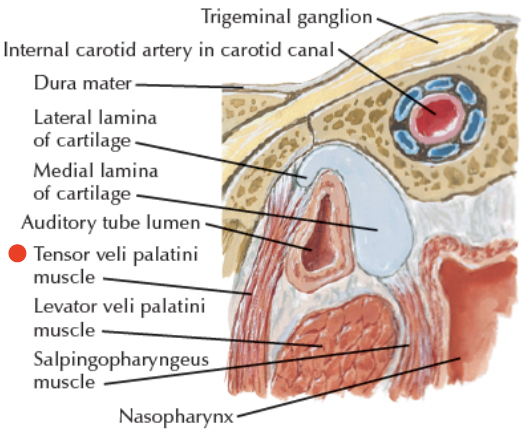

Pharyngotympanic tube

- 通過 Temporal bone

- 後2/3是軟骨

- 通過 Temporal bone

- 後2/3是軟骨

- Levator veli palatine m.

- From Scaphoid fossa

V3支配

- Tensor veli palatini m.

- 增加軟顎強度

- 打開耳咽管

- 繞過 pterygoid process

藍圈: Pharyngotympanic tube

綠: Tensor veli palatini m.